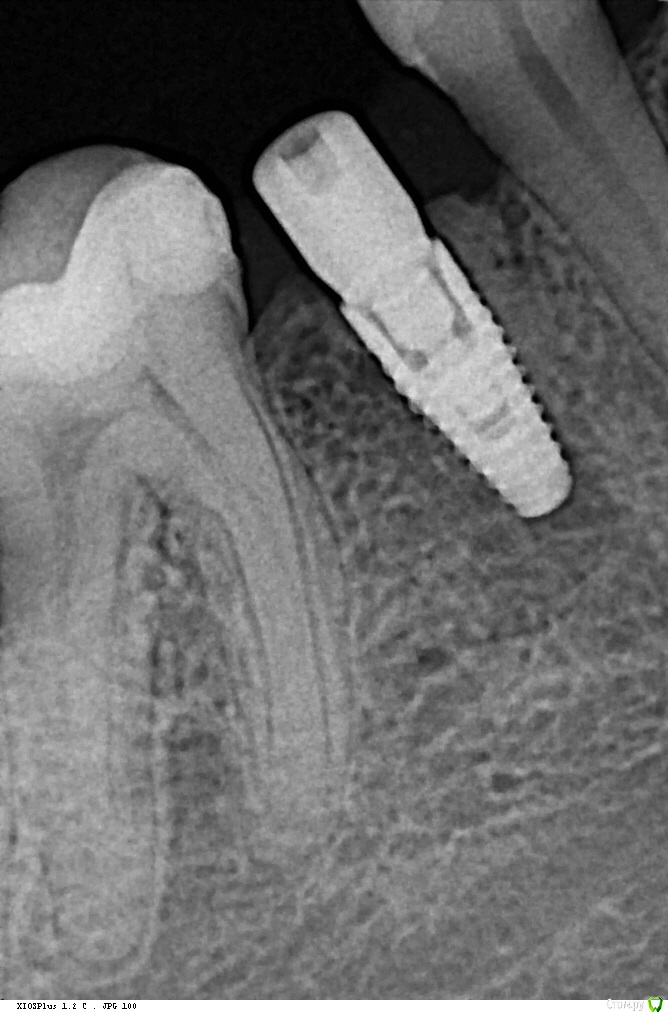

Кариес+ Опубликовано 26 июля, 2016 Поделиться Опубликовано 26 июля, 2016 Добрый день уважаемые коллеги. В область отсутствующего зуба 45 одномоментно после удаления был установлен имплантат нобель 3.5 с торком 35. Первый снимок сразу после установки, вторые через два месяца спустя Ссылка на комментарий

Кариес+ Опубликовано 26 июля, 2016 Автор Поделиться Опубликовано 26 июля, 2016 Смущает щель между импл и костью . Фиброинтеграция или незрелая не рентгеноконтрасная кость? Ссылка на комментарий

Fibez Опубликовано 26 июля, 2016 Поделиться Опубликовано 26 июля, 2016 (изменено) не спешите вынимать. ждите обычные 6 месяцев. это может быть и просто "засветка" от винта Изменено 26 июля, 2016 пользователем Fibez Ссылка на комментарий

TemTeam Опубликовано 27 июля, 2016 Поделиться Опубликовано 27 июля, 2016 не спешите вынимать. ждите обычные 6 месяцев. это может быть и просто "засветка" от винта +100частенько нарываюсь на подобную картину. первое время очень пугало. но начиная работать имплант оказывался очень даже стабилен. так что думаю рано еще переживать Ссылка на комментарий

Доктор Хаус Опубликовано 4 августа, 2016 Поделиться Опубликовано 4 августа, 2016 Ой тест делать с анестезией ? Вот если случай без фдм а с заглушкой ? Небольшую инфильтрацию дать чтобы заглушку убрать и поставить имплантовод и дать нагрузку в 30-35н/см ?Даже с проводниковой анестезией будет больно, если произошла фиброинтеграция . А она происходит от того костное ложе перегрето или косное ложе не конгруэнтно самому имплантату . Для себя я четко усвоил что при одномоментный имплантации около 4 х мм имплантата должно быть в кости . По прицельным снимкам у меня сложилось впечатление что имплантат закручен в лунку. И костного ложа , здесь как такового нету . Вполне вероятно, что здесь произошла фибро интеграция ( неприжился) и поэтому на прицельном снимке вокруг имплантата определяется зона пониженной плотности. Ссылка на комментарий

Evikrol Опубликовано 4 августа, 2016 Поделиться Опубликовано 4 августа, 2016 (изменено) выкрутите монитор на яркость, смотрите какой чёрный ореол даже вокруг ФДМ и эмали. Имхо артефакты. Возможно фильтр в проге по. Не нормальная картинка. ТС залейте любой другой снимок имплантата с вашего рентгена. Изменено 4 августа, 2016 пользователем Evikrol Ссылка на комментарий

Доктор Добрых Дел Опубликовано 6 августа, 2016 Поделиться Опубликовано 6 августа, 2016 Вообще не вижу разницы между 3мя снимками. И на первом и на втором видна "щель". Ссылка на комментарий